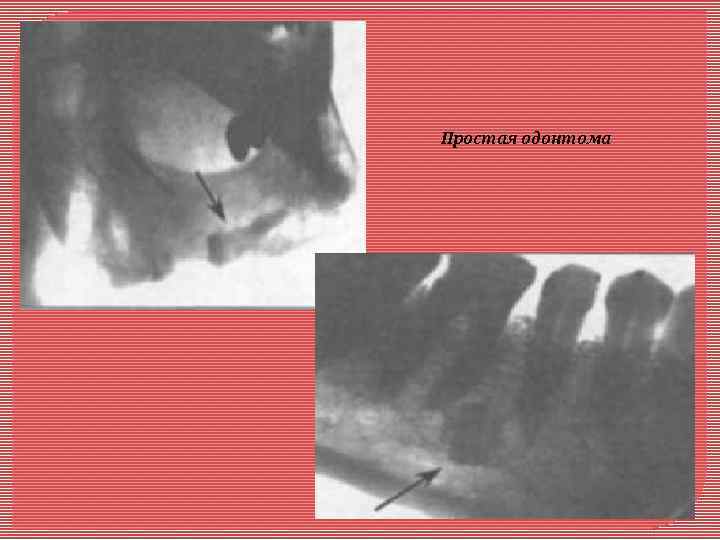

Одонтома - возникает в связи с нарушением развития в период формирования зачатков зубов. Локализация: чаще в верхней челюсти в области премоляров. Растет медленно. Макроскопически имеет капсулу, при больших размерах вызывает деформацию челюсти. Микроскопически различают простые и сложные одонтомы. Сложные одонтомы делят на смешанные (комплексные) и составные Простая одонтома представлена твердыми тканями одного зуба, соединенными а виде нароста в области корня или шейки сущест вующего зуба, «впаянного» в цемент. Может быть представлена зубом с незначительным нарушением топографии его твердых тканей. Сложные одонтомы развиваются из нескольких зубных зачатков. Смешанная (комплексная) одонтома представляет собой хаотичное по топографии сочетание твердых зубных тканей: эмали, дентина, цемента Составная это конгломерат спаянных друг с другом нескольких мелких рудиментарных зубов, в которых топография твердых тканей упорядочена, как в обычных зубах. Рентгенологическая диагностика одонтом не представляет особых трудностей. На фоне обычной костной ткани выявляется очень плотное, округлой формы образование, окруженное ободком просветления (за счет фиброзной капсулы). В зубном ряду, как правило, отсутствует один или несколько зубов.

Простая одонтома